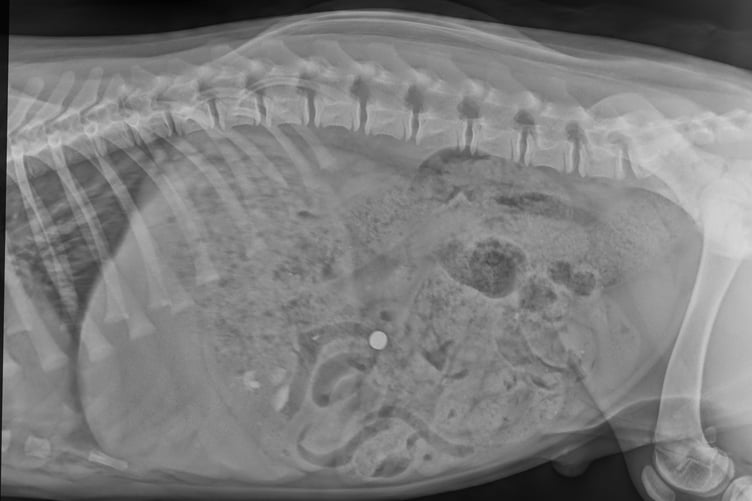

He was rushed off to St Peter’s Vet in Petersfield and following the X-ray surgeons were able to see the battery had travelled through his stomach and into his intestines.

“We made an incision in Warrior’s abdomen, but although the battery could be seen clearly on the X-ray, it proved tricky to find because a dog’s intestines are quite long and the battery was tiny – it only measured about 1cm across.

“My colleague had the brilliant idea to use a sterile magnet to locate the battery within Warrior's intestine. The magnet attached to the battery and once located we were able to guide the magnet through and out of his intestines.“